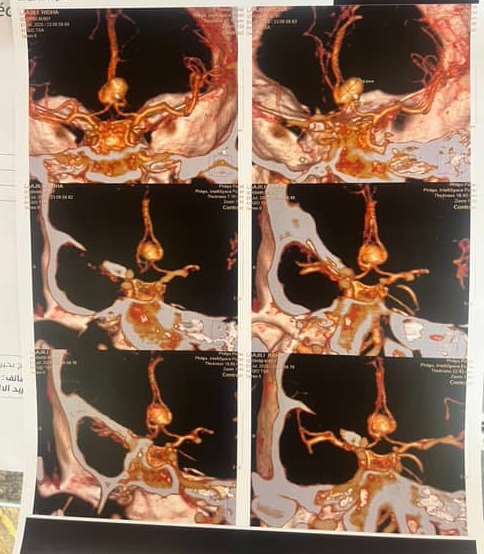

On July 23rd, our beloved father, Ridha, was found unconscious after hours of not responding. Earlier that day, he sounded confused — we thought he was just tired. But it was far worse: he had suffered a ruptured cerebral aneurysm, a life-threatening condition that needed immediate surgery.

At the first hospital, doctors misdiagnosed him and gave him aspirin, worsening the bleeding in his brain. By the time we got to a second hospital, precious hours had been lost. The public system couldn’t help — most neurosurgeons were away, and the one available wasn’t specialized. Our only option was a private clinic, but they refused to admit him to ICU without advance payment. Even after raising 20,000 dinars, they still said no — until public pressure and media involvement forced them to accept him.

On July 24th, Ridha finally underwent emergency brain surgery. He’s now in the ICU — stable, but still in critical condition. He’s uninsured, and each day in intensive care is pushing us further into debt, we're looking at 70,000 up until today.